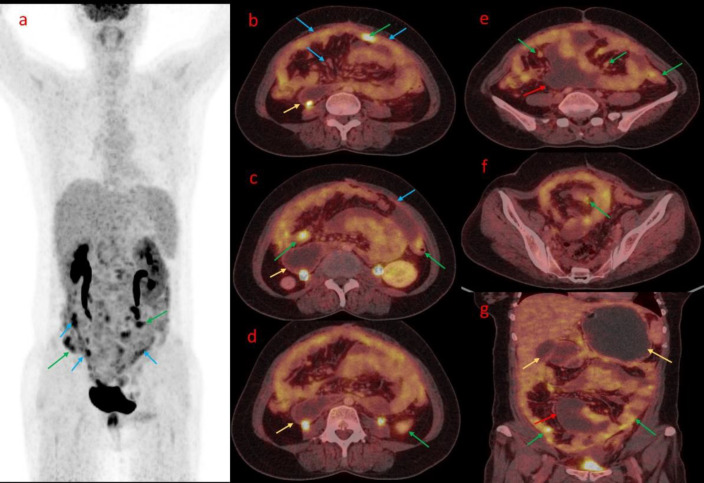

腹膜癌肿(PC)是癌细胞在腹膜中的扩散,是晚期胃肠道癌症和妇科癌症的一个重要问题。本病例系列包括 18F- 氟脱氧葡萄糖正电子发射断层扫描/CT(18F-FDG PET/CT)上 PC 的外观和模式。腹膜播散的主要来源是腹部或盆腔肿瘤的直接侵犯和远处肿瘤的转移扩散。准确的术前诊断和 PC 定量对确定适当的治疗方法起着至关重要的作用,尤其是在手术规划方面。术前评估采用了多种成像模式,如计算机断层扫描(CT)、磁共振成像(MRI)和 18F-FDG PET/CT。在这些方法中,18F-FDG PET/CT 显示了更好的解剖定位和病理结果性质的准确信息。本系列病例展示了四个病例,说明了 PC 在 FDG PET/CT 上的成像特点。FDG PET/CT 在诊断和评估 PC 方面发挥着重要作用,有助于 PC 的检测、分期和治疗计划。它在识别和描述病变以及在原发肿瘤位置不明的情况下检测原发肿瘤部位方面超越了传统的成像技术。此外,FDG PET/CT 还有助于评估治疗反应和监测疾病进展,为了解治疗效果和指导患者管理决策提供依据。

Peritoneal carcinomatosis (PC), the spread of cancer cells in the peritoneum, is a significant concern in advanced gastrointestinal and gynecological cancers. This case series includes findings on the appearance and pattern of PC on 18F-fluorodeoxyglucose positron emission tomography/CT (18F-FDG PET/CT). The primary sources of peritoneal dissemination are direct invasion from abdominal or pelvic tumors and metastatic spread from distant tumors. The accurate preoperative diagnosis and quantification of PC play a vital role in determining the appropriate treatment approach, with a particular emphasis on surgical planning. Several imaging modalities have been employed in preoperative evaluation, such as computed tomography (CT), magnetic resonance imaging (MRI), and 18F-FDG PET/CT. Among these modalities, 18F-FDG PET/CT has demonstrated improved anatomical localization and accurate information about the nature of pathological findings. The case series showcases four cases that illustrate the imaging characteristics of PC on FDG PET/CT. FDG PET/CT plays a vital role in diagnosing and assessing PC, aiding in its detection, staging, and treatment planning. It surpasses conventional imaging techniques in identifying and characterizing lesions and detecting the primary tumor site in cases where its location is unknown. Furthermore, FDG PET/CT additionally assists in evaluating treatment response and monitoring disease progression, providing insights into treatment effectiveness and guiding patient management decisions.